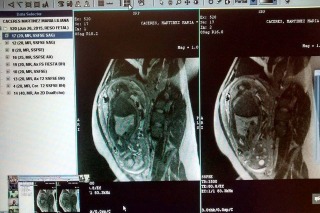

Desde Formosa fueron transmitidas al Hospital Posadas imágenes de resonancia magnética de una paciente con 36 semanas de gestación, con un defecto de cierre de la columna lumbo sacra (mielomeningocele).

El equipo interdisciplinario del Hospital Posadas pudo así debatir la conducta a seguir con el embarazo y determinar una posible derivación de la paciente al servicio de alta complejidad.